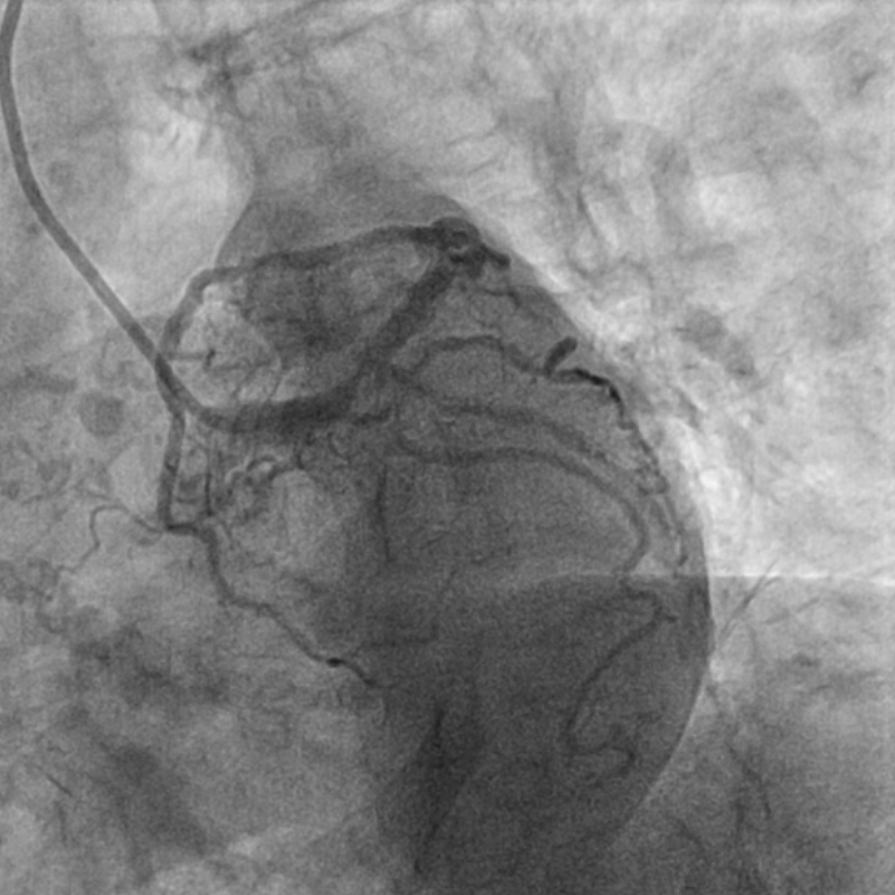

图2 术前造影提示多处再狭窄,冠脉钙化明显

该患者入院后,完善相关检查并再次建议行CABG治疗,但家属仍拒绝,遂考虑再次行PCI手术干预。冠脉造影提示患者冠脉右冠状动脉中段70-95%再狭窄,左主干末端80%狭窄,前降支原支架中远段 80-95%再狭窄,回旋支完全闭塞,急需手术尽快解决冠脉血流灌注问题,否则随时有生命风险,但患者多处支架内/节段内再狭窄,造影提示钙化明显,外院已尝试无法扩张,经手术团队充分讨论后,计划在IABP支持下,先进行右冠状动脉干预,利用IVUS精准评估原支架再狭窄部位情况,采用旋磨或Shockwave冲击波球囊处理无法扩张的病变部位,右冠处理后择期进行左冠状动脉干预。在制定了详尽的手术计划后,手术团队首先对患者的右冠状动脉行IVUS检查,结果提示该患者右冠中段支架局部膨胀不良,局部支架面积6.67mm²,管腔内多处可见钙化小结及270°以上钙化,IVUS钙化积分达3分。由于膨胀不良处原支架后方可见钙化斑块,常规旋磨效果不佳,对于此类钙化病变,IVL处理是最佳方案。手术团队对近端采取棘突球囊及高压球囊进行扩张,采用Guidezilla辅助下输送3.0mmx12mm Shockwave冲击波球囊于右冠钙化处进行冲击波钙化斑块碎裂术,通过IVUS证实支架内的新生钙化病变得到松解,原膨胀不良部位支架面积达到7.76mm²,后经过高压球囊充分预处理,顺利完成右冠支架植入,术后复查右冠原膨胀不良部位支架面积9.17mm²。